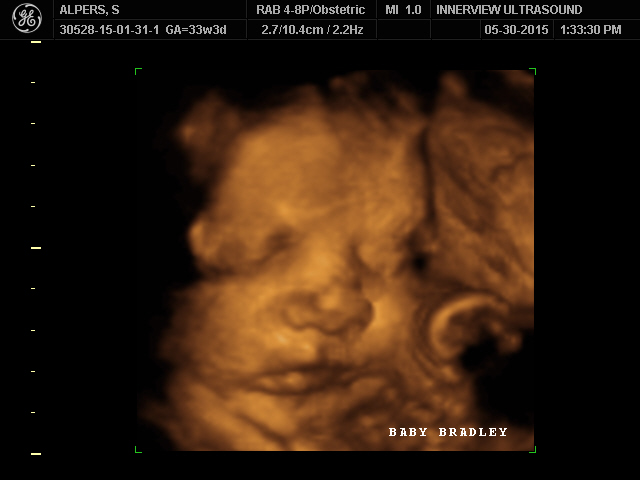

Mine I was 33+4 weeks the experience was nice very large room and they had a large tv at the end of the room were you can see the video that way everybody won't be al over the tech besides the tech voice being really high pitched I enjoyed it lol and loved seeing my LO.

The second picture is my first born when he was 4 months and the bottom is the new addition :)